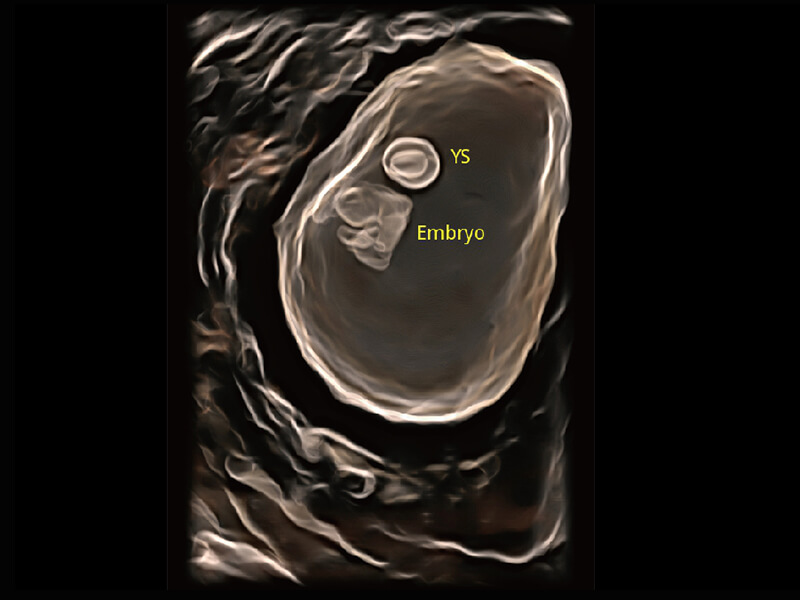

S60探头工艺,从前端信号处理每一个环节采集无损声学数据,真实还原组织原貌,再现解剖细节。